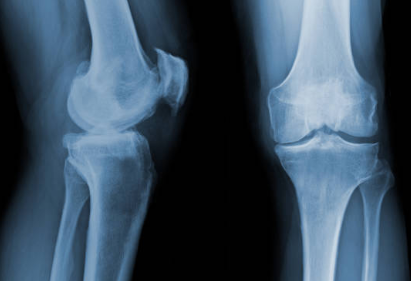

5) O다리, X다리 같은 다리 정렬 문제

다리 정렬이 틀어져 있으면 체중이 무릎 안쪽 또는 바깥쪽으로 쏠리게 돼요.

그 쏠리는 부위는 연골이 더 빨리 닳을 수밖에 없지요.

평소 걸을 때 신발 바닥이 한쪽만 닳는 분들은 무릎도 한쪽이 더 빨리 아파질 수 있어요.

2) 과체중(체중 증가)

무릎은 체중을 그대로 받는 관절이라서, 체중이 늘면 그 부담이 아주 크게 느껴져요.

특히 계단이나 쪼그려 앉기 같은 동작에서는 무릎에 체중의 몇 배 압력이 가해질 수 있어요.